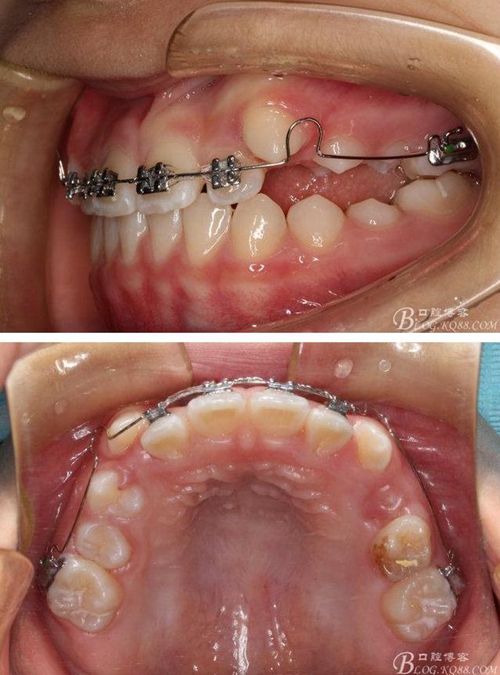

矯治第7個月復(fù)診:磨牙已有咬合接觸。上頜兩個6貼粘貼頰面管,矯治裝置成為真正的“2×4”矯治器。因為上頜兩個3唇側(cè)錯位為完全弓外牙,所以在上頜弓絲上彎制了彎曲進(jìn)行避讓。兩個頰面管的近中設(shè)置了“阻擋曲”,目的是使上頜前牙進(jìn)一步唇移,同時為側(cè)方牙齒的萌出創(chuàng)造空間。停止使用固定式低位唇弓Activator。